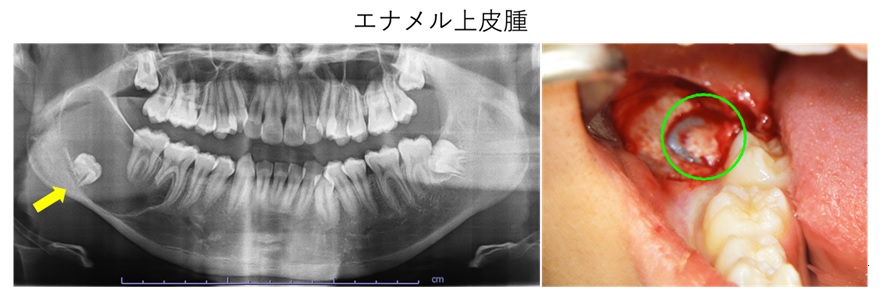

口腔腫瘍・嚢胞

口腔腫瘍は、口腔内に発生する異常な組織増殖を指します。腫瘍は良性と悪性があり、良性腫瘍は一般的にゆっくり成長し、転移しませんが、悪性腫瘍(口腔癌)は速やかに増殖し、転移する可能性があります。嚢胞は液体や半液体が入った袋状の構造で、感染や炎症、外傷が原因となることがあります。

治療法は、腫瘍や嚢胞の種類と大きさ、場所によって異なります。口腔内の異常に気づかれた場合は、ご相談ください。